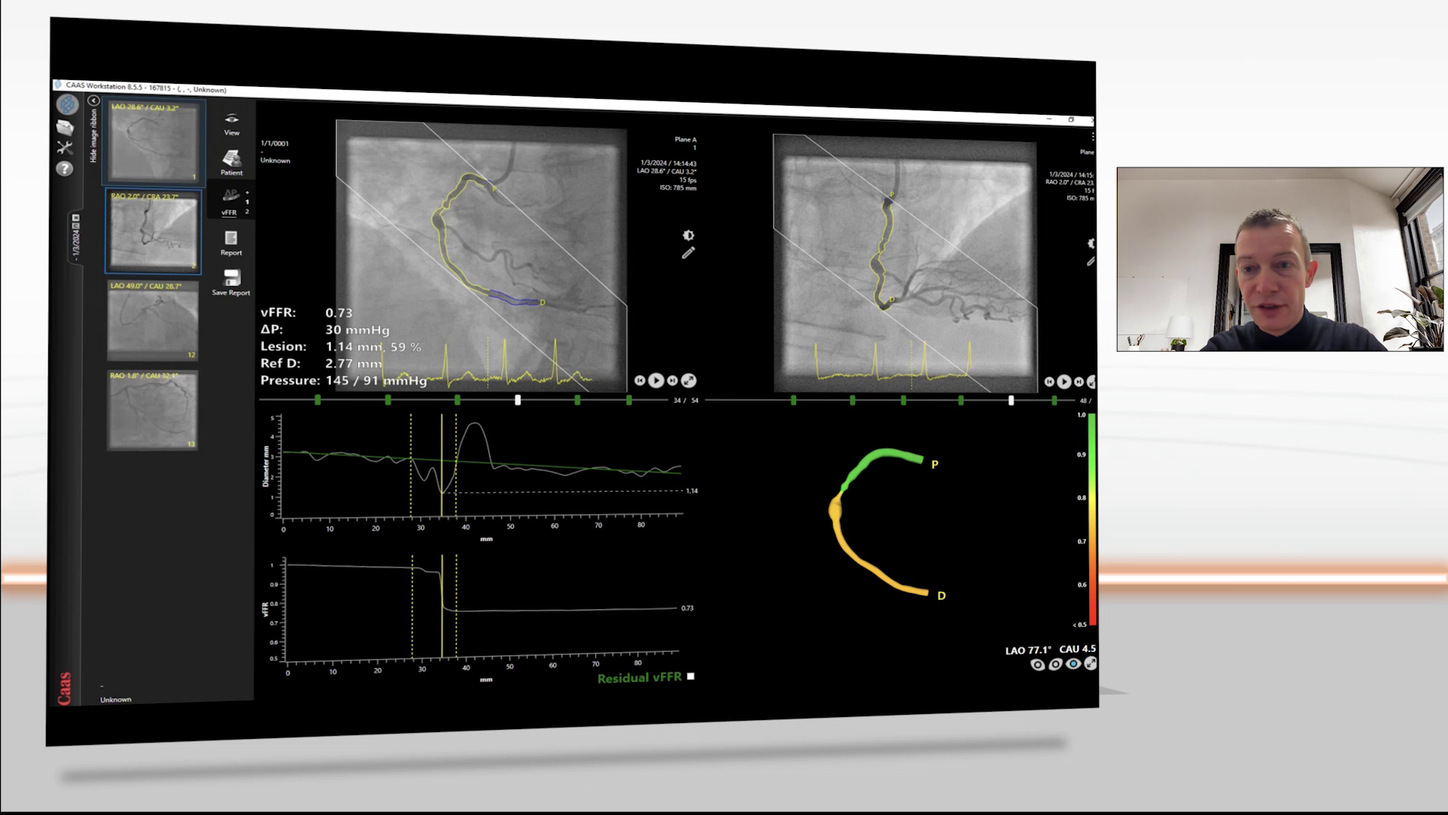

QuantWeb vFFR - integration of angio-based FFR

QuantWeb vFFR

Integration of angio-based FFR

Courtesy of University of Tokyo Hospital, Japan

Less invasive angio-based FFR calculation tool vFFR

•  calculates the pressure drop in the coronary arteries;

• is a fast and easy-to-use tool to assess the hemodynamic relevance of stenoses;

• shows high correlation with FFR and high inter-observer reproducibility.